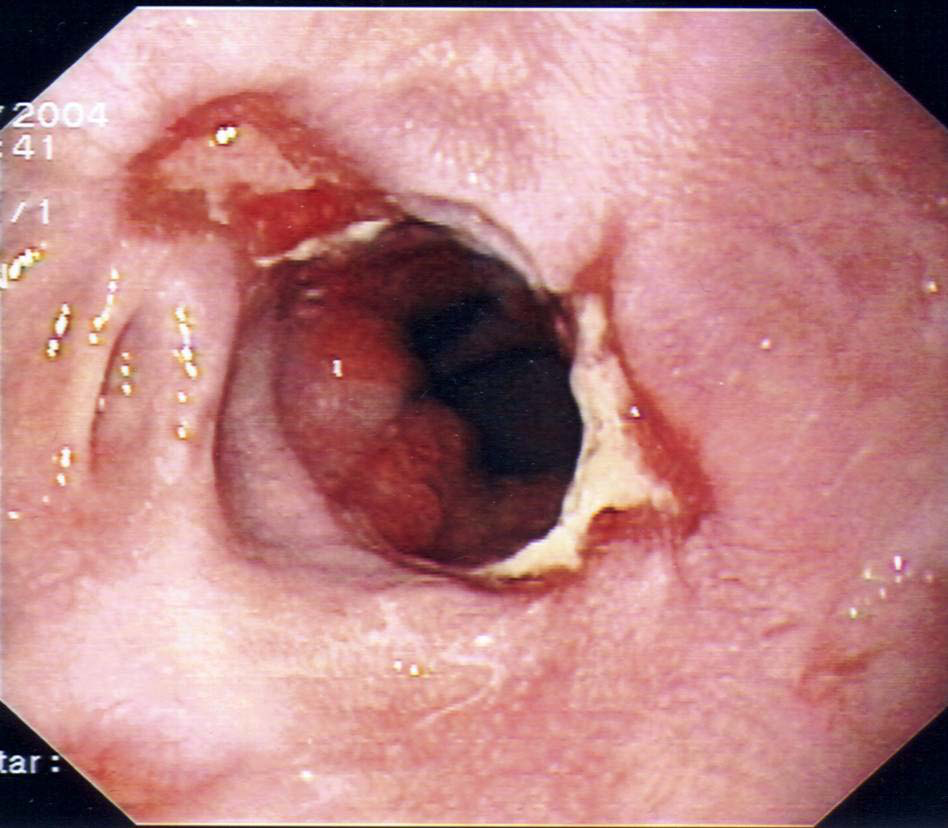

2) Μια ενδοσκοπικη μελέτη (γαστροσκοπηση) χρήσιμη στη διερεύνηση οισοφάγου και στομάχου .

Εικονες απο αξονικη τομογραφια και ενδοσκοπηση

Ταξινόμηση της οισοφαγίτιδας κατά LA

Λύσεις της συνέχειας του βλεννογόνου μικρότερης των 5 mm σε μήκος βαθμός Α , μεγαλύτερης των 5 mm σε μήκος βαθμός Β, λύσεις του βλεννογόνου και των πτυχών σε ποσοστό μικρότερο του 75 % της περιφέρειας του οισοφάγου βαθμός C, διάβρωσεις που εκτείνονται μεγαλύτερα του 75% της περιφέρειας του οισοφάγου βαθμός D.